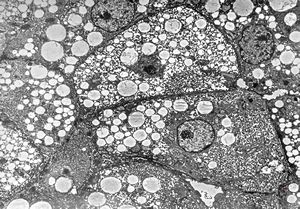

F,1y. | steatosis - Reye hepatocerebral syndrome